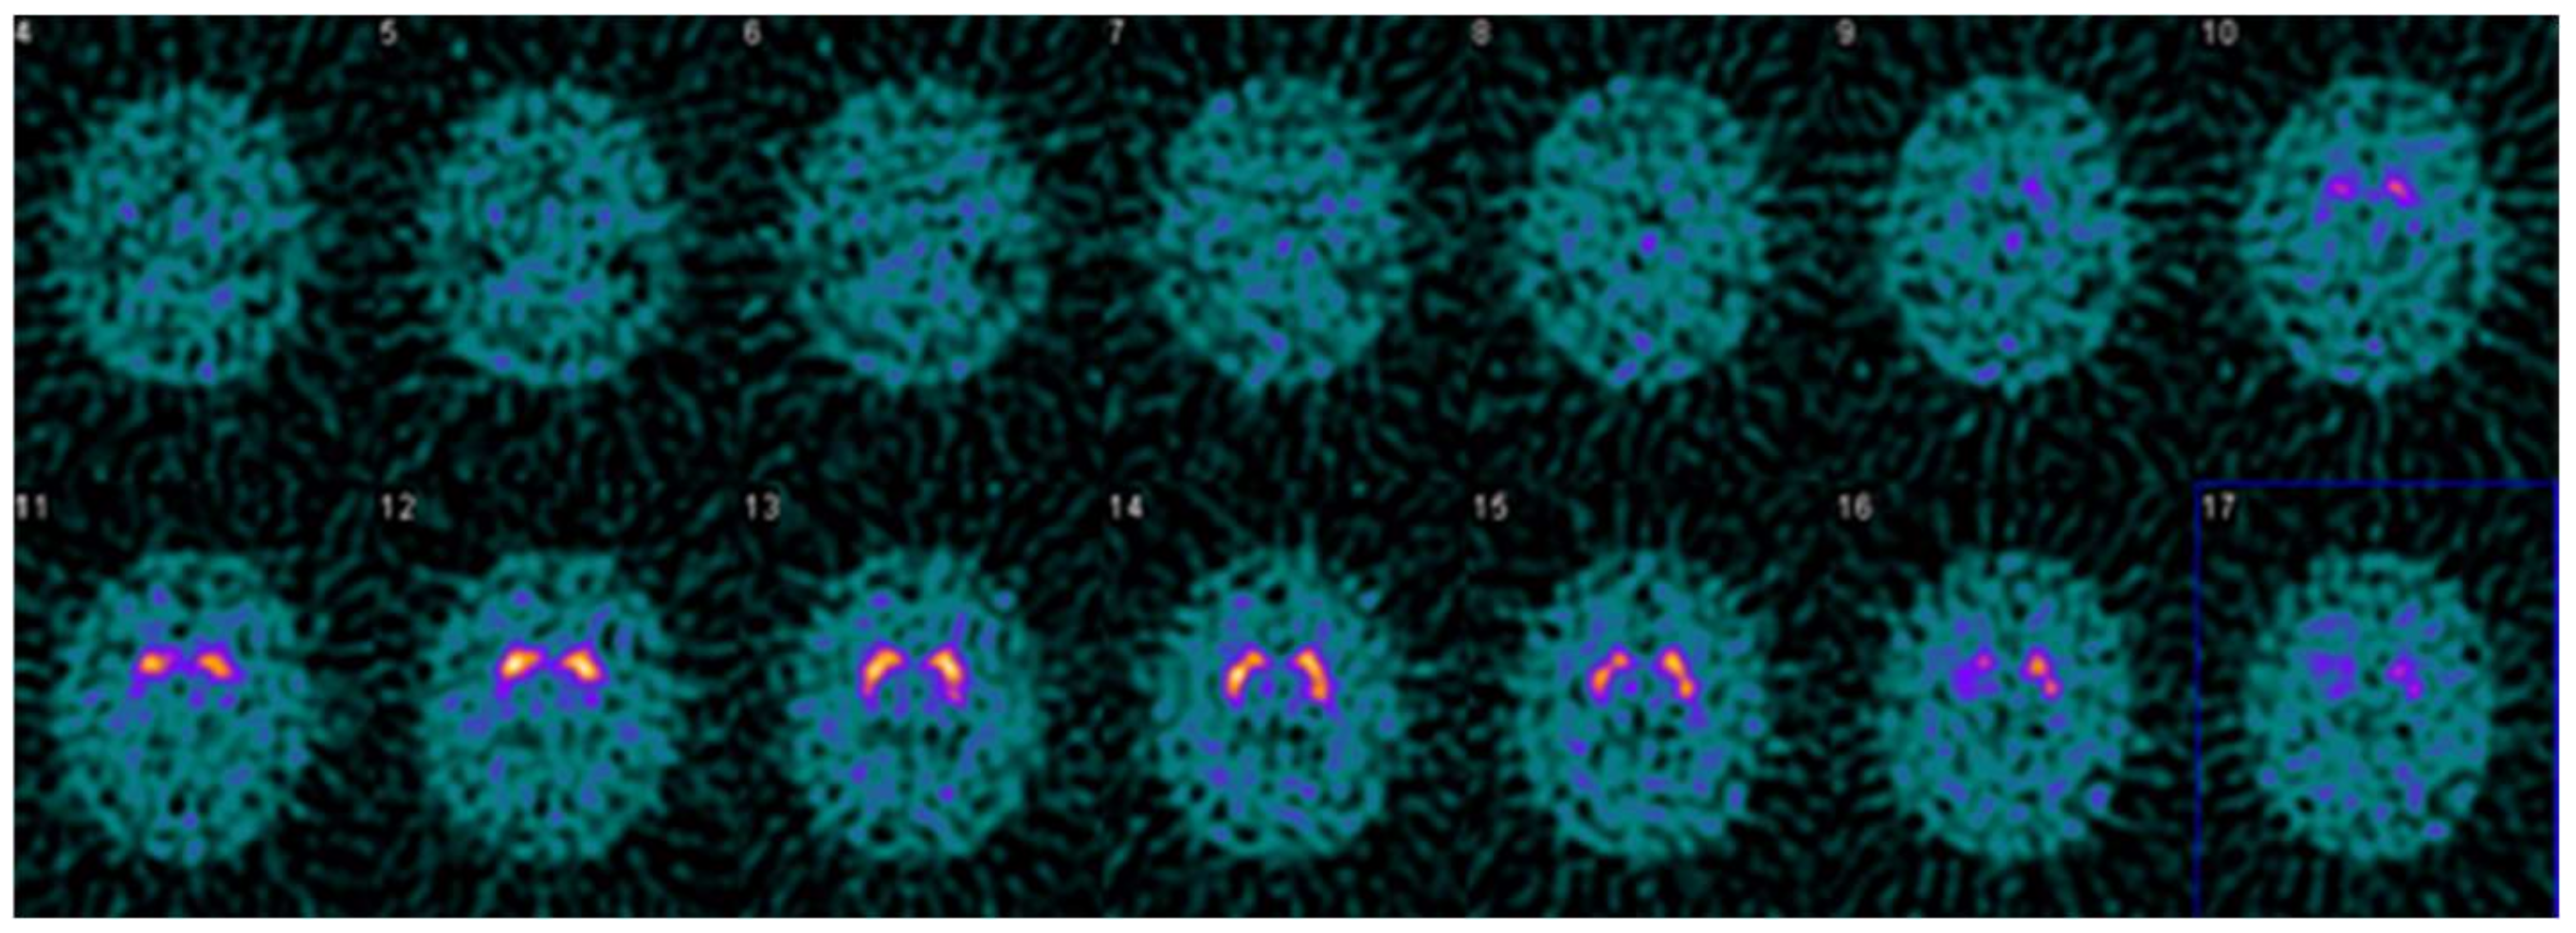

Figure 5.

Example DaTQUANT results in a non-PS patient demonstrating visually normal appearing striatum bilaterally. However, the right posterior putamen z-score is −2.15, meeting the threshold for a diagnosis of PS. This is an example of false-positive quantification, reinforcing the idea that quantification is a useful tool for interpretation, but should not replace visual evaluation. Interestingly, the SBR (1.27) does not meet the threshold for PS, and the percent deviation (−0.35) is right at the threshold value for the optimal model (≤−0.36).